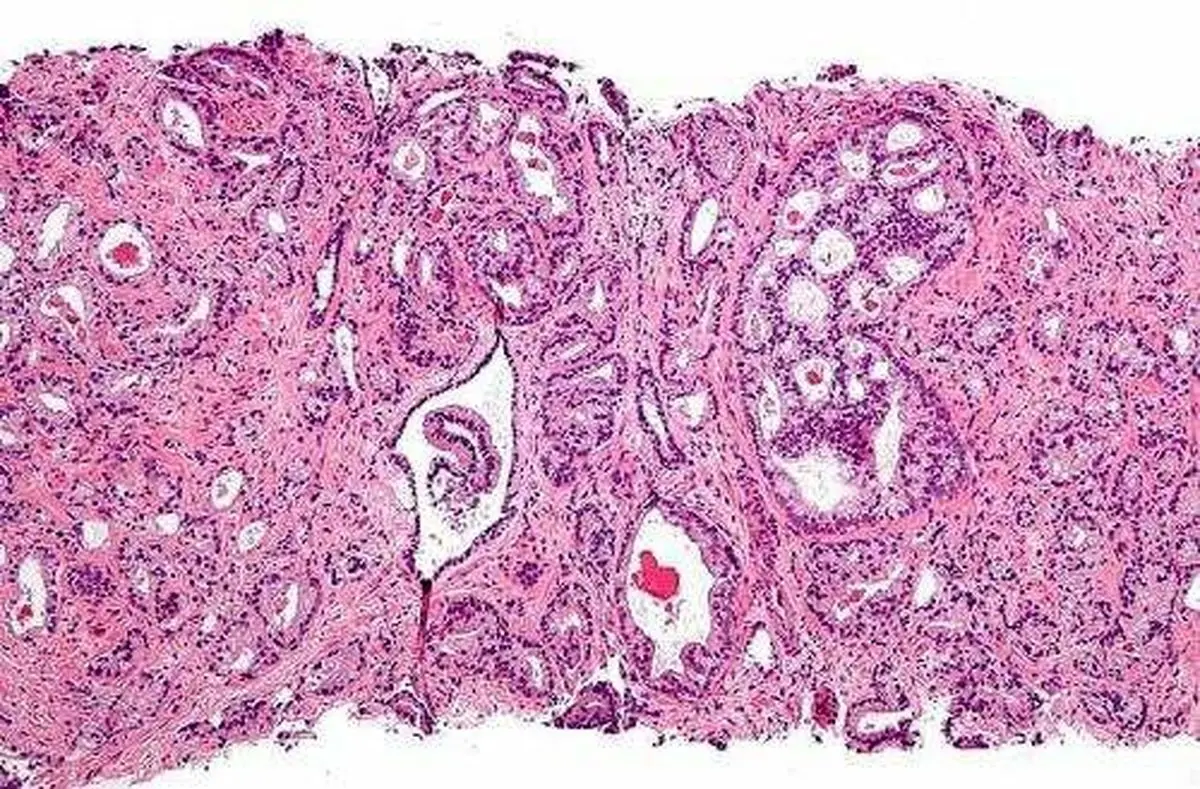

پژوهشگران دانشکده پزشکی "دانشگاه بوستون"(BUSM) دریافته‌اند که متوقف کردن نوعی پروتئین می‌تواند راهبرد امیدوارکننده‌ای برای پیشگیری از گسترش سرطان پروستات باشد.

پژوهشگران، بررسی بلند مدتی روی خانواده سه پروتئین موسوم به" BRD2"، "BRD3" و "BRD4" که در تنظیم بیان ژن نقش دارند، انجام دادند تا تأثیر عملکرد آنها را بر سرطان نشان دهند. آنها دریافتند که توقف پروتئین BRD4، نقش مهمی در حرکت و تهاجم سلول‌های سرطان پروستات دارد.

CRPC، یکی از انواع تهاجمی سرطان پروستات است که اغلب به گسترش کشنده متاستاز منجر می‌شود. در درمان استاندارد بیماران مبتلا به CRPC، معمولاً سیگنال‌دهی گیرنده‌های آندروژنی مختل می‌شود اما این نوع درمان با وجود تأثیری که در دو تا سه سال گذشته از خود نشان داده، معمولاً به خاطر مکانیسم مقاومتی گیرنده‌های آندروژنی، در توقف گسترش سرطان پروستات شکست خورده است.

CRPC، یک بیماری پیچیده است که گیرنده‌های آندروژنی و الگوی بیان ژن متفاوتی دارد. سلول‌های تومور پروستات با پیشرفت بیماری، وابستگی کمتری نسبت به سیگنال‌دهی گیرنده‌های آندروژنی پیدا می‌کنند و مکانیسم سیگنال‌دهی جایگزین را برای حفظ رشد و انتشار سرطان به کار می‌برند.